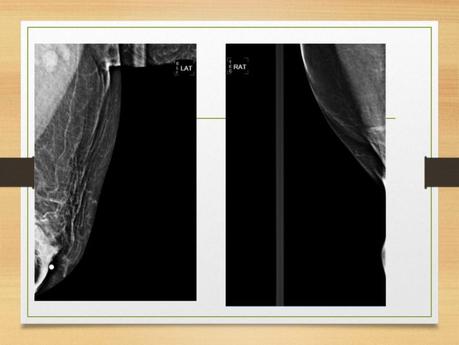

•PROYECCIONES MAMOGRAFICA •M.A.M FRANCISCO GUILLERMO COSME VASQUEZ. •17-ENE-2019 •Proyecciones mamográficas •Un buen posicionamiento conlleva a una buena interpretación radiológica. •La dosis promedio glandular no debe exceder de 3 mGy. •Las imágenes mastograficas no deben presentar defecto alguno. •Imágenes de calidad requieren técnicos altamente motivados. • •El numero de proyecciones hoy en día pueden ser clasificados en tres categorías: •A) proyecciones estándar utilizadas en el tamizaje: cc y mlo •B) las proyecciones que ubican la posición exacta de una anormalidad en la mama. •C) proyecciones utilizadas para definir la naturaleza de la anormalidad •Posiciones •Sentada o de pie. •Pendular: inclinada hacia adelante. •prono. •El brazo colgado hacia adelante: relaja el m. pectoral mayor. • • •La mama debe comprimirse hasta que el tejido este tenso •Tocar la mama por un costado •La piel no debe hundirse •La compresión no debe ser dolorosa •Compresión •Proyecciones básicas •Craneocaudal (cc) •Oblicua mediolateral (OML) • •Craneocaudal •Colocar la mama medial •Elevar pliegue inframamario, ajustando la altura del receptor. •Usando ambas manos jalando y colocando encima del receptor •Muestra las partes interna y externa de la mama. •Se obtienen imágenes de ambas mamas por separado. •Paciente de pie o sentada. • •Se levanta la mama para lograr un ángulo de 90° con la pared torácica. •Se tracciona la mama hacia adelante con el pezón de perfil. •El brazo del lado evaluado se debe relajar, con el hombro hacia atrás. •La cabeza es girada lejos del lado evaluado. •Dejar la mama opuesta sobre la esquina del receptor •Px inclinada hacia delante, con la cabeza hacia un costado del tubo. •La piel debe deslizarse sobre la clavícula •Jalar el tejido lateral sin perder tejido medial • •Una proyección óptima requiere: •A) visualizar las porciones externa e interna de la mama, •B) Visualizar grasa de Chaissagnac •C) Visualizar el pectoral mayor •D) Visualizar el pezón bien alineado. • •Oblicuo medio lateral •Paciente de pie o sentada. •Ambas mamas por separado. •El rayo central entra perpendicular al músculo pectoral de la paciente. •Se debe determinar el grado de oblicuidad del musculo pectoral entre 45 y 60 grados. • • • •La paciente de frente al mastógrafo, coloca el brazo del lado evaluado hacia adelante y la mano hacia el frente. •Se tracciona la mama y el m. pectoral anterior y medialmente, lejos de la pared torácica. •Aplicar compresión con la mama lejos de la pared torácica y hacia arriba. •El borde superior debajo de la clavícula y el borde inferior incluirá el pliegue infra mamario •La paciente puede retraer la mama opuesta con la otra mano. • • •Criterios de evaluación: • a) Debe verse todo el tejido mamario •b) el musculo pectoral se debe encontrar a la altura del pezón •c) el patrón del parénquima debe observarse a 90 grados •d)Demostrar pliegue inframamario •e) región axilar visible •f) pezón perfilado •g) área glandular y adiposa adecuadamente penetradas. •Proyecciones especiales •Lateral a 90 grados •Cono de compresión •Magnificacion •Craneocaudal exagerada •Escote •Cola axilar •Tangencial •giro • •Mediolateral •Útil en patologías en la cara central o lateral de la mama. Para confirmar una anomalía observada en la OML. •calcificaciones •Aire •Niveles de liquido •Localizar lesiones en plano sagital •Eliminar sobreposiciones •De pie o sentada. •El RC es angulado a 90°. • • •La paciente frente al mastografo coloca el brazo del lado a examinar hacia adelante la mano sobre la barra hacia el frente. •Se tracciona la mama y el m. pectoral anterior y medialmente. El pezón de perfil. •Aplicar compresion. •Traccionar el tejido abdominal hacia abajo. •La paciente retrae la mama contralateral con la mano opuesta. • •La imagen debe incluir todo el tejido mamario, •la region axilar y •el m. pectoral. • •Craneocaudal exagerada (lateral CCEL) •Es la proyeccion mas solicitada cuando la CC no muestra todo el tejido axilar o cuando se observa una lesion en la OML pero no en la CC. •Se inicia como una CC, luego se rota el cuerpo ligeramente para incluir mas axila. •La mano al frente, relajar el hombro. •La cabeza lejos del lado a explorar. •Si la lesión es lateral se debe tomar una CCE medialmente. •Craneocaudal exagerada (lateral CCEL) •Es la proyeccion mas solicitada cuando la CC no muestra todo el tejido axilar o cuando se observa una lesion en la OML pero no en la CC. • •Proyección con desplazamiento de implante (Ecklund) •Lesiones subyacentes al implante. •Complicaciones como pérdida intracapsular o extracapsular del implante. •No puede lograrse una compresión firme. •Se realiza después de las proyecciones básicas. •El método de Eklund consiste en empujar el implante hacia la pared torácica. • •Proyección axilar •Se usa para aislar la cola axilar y cualquier lesión dentro de esta. •El tubo se debe colocar paralelo a la axila. •Los tejidos laterales se incluyen en el campo de la imagen. •Solo se comprime la cola de la mama. • • •Proyección del surco •Visualiza el tejido y la porción mas medial de los cuadrantes internos. •Se colocan las dos mamas en posición horizontal. •Se aplica compresión. • •Cono de Compresión •Reduce el grosor de un área en específico. •Se realiza en la proyección donde se observa la lesión en estudio. Se mide la distancia de la lesión al pezón. •Se aplica los platos pequeños para realizar la compresión. •Generalmente se combina con magnificación •Magnificación •Agrandar áreas específicas de interés •Lesiones pequeñas •Microcalcificaiones. •Tubo de rayos x con un foco de 0.1mm •Agrandamientos de 1.5 a 2 veces •Se puede utilizar en la mayoría de las proyecciones mamográficas. •Magnificación •Se acerca el foco a la mama alejando el detector. •Se puede realizar en todas las proyecciones. •Se efectúa para compresión focal o localizada • •Mama masculina •Posición de la mama masculina •Se coloca similar a una mama femenina pequeña. •La OML se usa para obtener imágenes en proyección lateral. •La CC se puede hacer caudocraneal. • • • • •